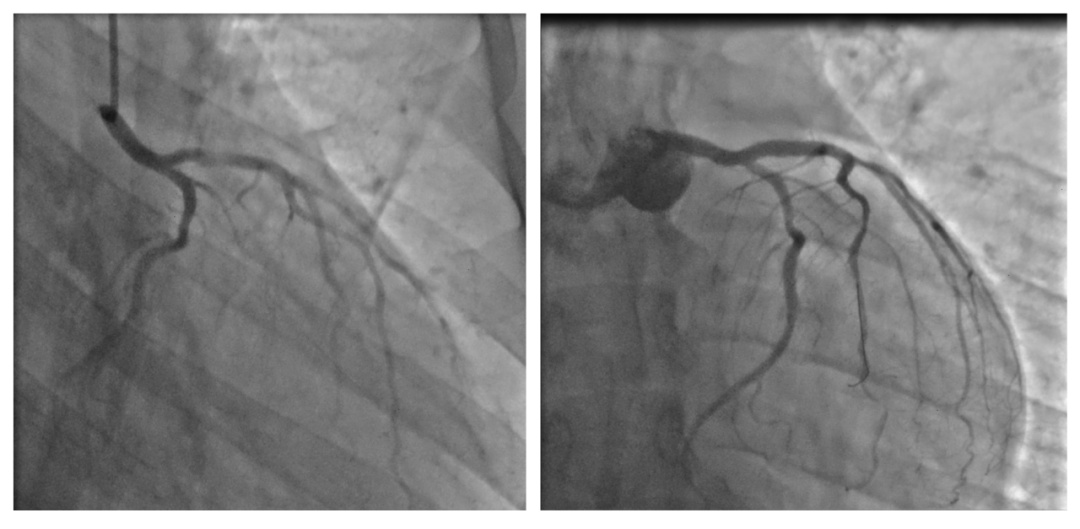

傍晚时分,急诊警报突然响起,医院有两位心肌梗死患者。在朱志栋医生的指导下,马彦成医生、陈伟明医生和胡锦涛医生为患者顺利实施了急性心肌梗死的紧急血管开通手术。

急性前壁心梗患者

左前降支血栓形成 PCI顺利开通血管